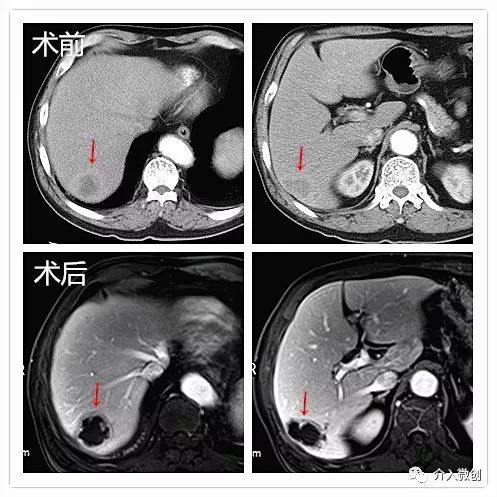

病例1

老年男性,诊断为右肺癌并纵隔淋巴结、肝多发转移。活检病理示:大细胞性未分化癌。肺部病灶经姑息性放化疗后有所控制,但肝脏病灶出现进展,遂行载药微球栓塞治疗。

复查MRI显示病灶大部分坏死

复查PET-CT亦提示病灶大部分已无活性,仅病灶下缘残存少许活性,后续行局部放射性粒子植入控制